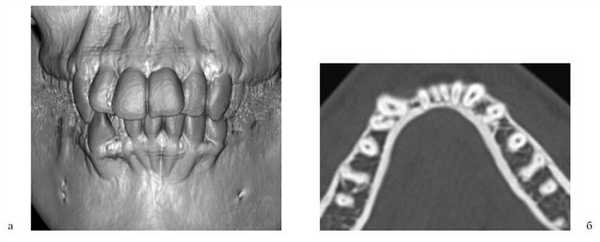

Ортодонтическое лечение после костной пластики проводилось под контролем за состоянием аутотрансплантата с помощью дополнительных методов диагностики — ЭОМ, УЗИ, спиральной компьютерной томографии (СКТ), что позволило оценить степень остеоинтеграции, либо резорбции костного регенерата (рис. 3).

Рис. 3. СКТ: 3D-реконструкция (а), аксиальный срез через 4 года после костной аутопластики (б), выделенный объем костного регенерата (в).

По окончании периода ретенции ортодонтическое лечение было направлено на нормализацию положения зубов, формирование оптимальной окклюзии (рис. 5, а—г).

Рис. 5. Этапы ортодонтического лечения по окончании периода ретенции. а — до костной пластики; б—г — перемещение небно расположенного бокового резца в костный регенерат; д, е — имплантат в области костного регенерата.

При адентии бокового резца в область костного регенерата вводили имплантат (см. рис. 5, д, е).